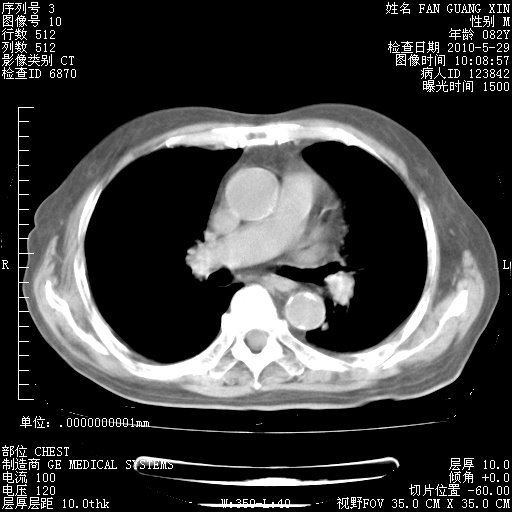

还需要哪些辅助检查?我们医院排除真菌感染没有任何检验方法,胸片好像能够排除肺部真菌感染。